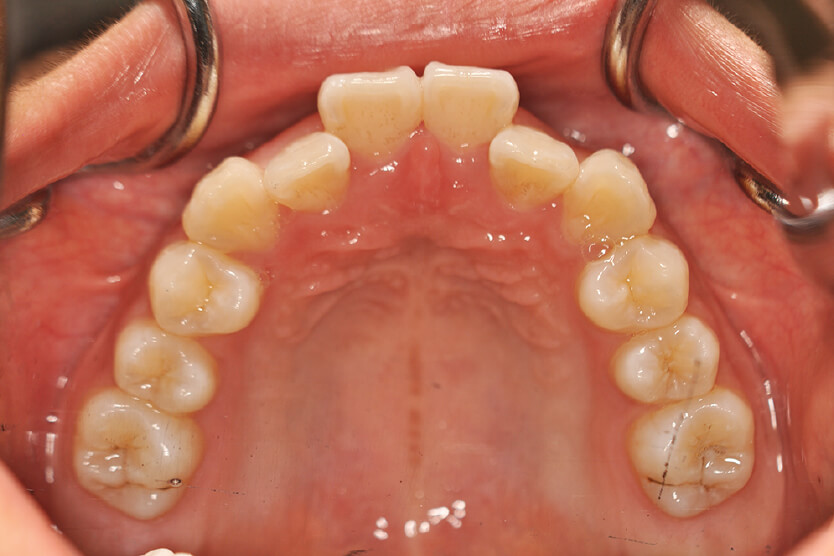

| 治療内容の詳細 | 初診時12歳の女性で、上顎前歯部の反対咬合を気にされ来院されました。 検査の結果、下顎前突、上顎前歯部叢生および上顎側切歯反対咬合を伴うアングルⅢ級不正咬合と診断しました。 治療としては、リンガルアーチを使用して、上顎側切歯を前方へ移動させ、反対咬合の改善を行い、マウスピース型矯正装置(インビザライン)で配列を行いました。 治療期間は1年5か月でした。 |